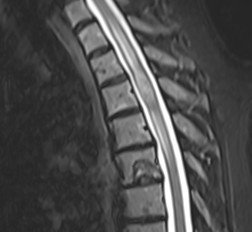

Pacientă în vârstă de 54 ani, cu un istoric îndelungat de neoplasm mamar, care acuză scăderea forței musculare în membrul inferior drept. RMN de coloană toracală a evidențiat o tumoră intramedulară T3-T4 de cca. 20/9/8 mm, centrală, relativ bine delimitată, care captează substanța de contrast – aspect sugestiv pentru o determinare secundară (metastază).

Intervenția chirurgicală a avut loc în bune condiții, reușind să extirpăm în cvasitotalitate țesutul tumoral fără a agrava pacienta din punct de vedere neurologic. RMN-ul de control efectuat a doua zi a confirmat absența rezecția completă precum și absența complicațiilor postoperatorii. Din punct de vedere neurologic, evoluția a fost favorabilă, cu ameliorarea treptată a deficitului motor sub kinetoterapie, pacienta putând fi mobilizată începând cu a doua zi postoperator, ulterior putându-și continua tratamentul oncologic: radioterapie spinală, apoi chimioterapie sistemică și interatecală.